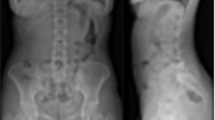

The study was performed at one of the core hospitals in our city. The hospital has surgical and out-patient departments. The out-patient department adopts a complete referral system; therefore, only patients who have a referral letter go to the hospital for consultation. A total of 281 consecutive LBP patients were registered consecutive LBP patients from June 2015 to December 2019 during their first visit. LBP was defined as a pain localized between the costal margin and the inferior gluteal folds. Radiography of the lumbar spine and pelvis at a standing position were evaluated for all patients. Lumbar MRI examinations were added and evaluated for LBP cases with buttock and/or lower limb pain as well as severe LBP cases without buttock or lower limb pain. Following these radiological evaluations, patients who had an infection or tumor in the lumbar spine or pelvis were excluded. We excluded 24 cases of metastatic lumbar spine tumor and 7 cases of lumbar infectious spondylitis/discitis. Finally, a total of 250 patients were included in the study. Subsequently, an analgesic periarticular SIJ injection was administered in order to diagnose and evaluate patients who indicated buttock pain in the region from the posterior iliac crest to the inferior gluteal fold and with positive result on either the Patrick’s test or the SIJ shear test. We defined the SIJP group (n = 53) as those who experienced unilateral buttock pain and fulfilled the criteria described here, as defined in our previous report10. The non-SIJP group (n = 197) was defined as those who had experienced LBP due to reasons other than SIJP. We used a self-written questionnaire to collect patient background information that included age, sex, height, weight, and smoking habits. The body mass index (BMI) was calculated using height and weight data. The first author measured spinopelvic parameters such as PI, PT, SS, and lumbar lordosis (LL) using the radiographs. We compared and analyzed the demographic characteristics and spinopelvic parameters of both groups. The medical/ethics review board of Kanto Rosai Hospital approved the study, including any relevant details, and confirmed that all experiments were performed in accordance with relevant guidelines and regulations and that informed consent was obtained from all participants.

There were no significant differences in the demographic characteristics (age, BMI, and smoking habits) between the groups except for sex. The ratio of female participants was significantly higher in the SIJP group than that in the non-SIJP group (P = 0.0179). Among the continuous variables, PI and SS were normally distributed, whereas age, BMI, PT, and LL were not normally distributed. There were significant differences in PI (P = 0.0122), SS (P = 0.0034), and LL (P = 0.0078) between the groups (Table 1). The detection powers for PI, SS, and LL were 0.71, 0.84, and 0.66, respectively. The mean PI values were significantly higher for female than for male participants (51.6° ± 12.0° vs. 47.9° ± 9.3°; P = 0.0089). The mean SS values for female and male participants were not significantly different (34.0° ± 9.5° vs. 33.0° ± 8.1°; P = 0.3789). Logistic regression analyses of 250 radiographs, after an adjustment for age and sex, revealed significant differences in PI (P = 0.0308) and SS (P = 0.0153) between the groups, with odds ratios of 1.03 and 1.05, respectively (Table 2). Among each of the spinopelvic parameters, SS and LL showed a strong correlation coefficient of 0.764, followed by a correlation coefficient of 0.676 for PI and SS (Table 3). The ROC analyses demonstrated that the AUC, cutoff, sensitivity, and specificity values were 0.60971, 50, 0.660, and 0.538, respectively, for PI, and 0.63006, 38, 0.509, and 0.736, respectively, for SS.